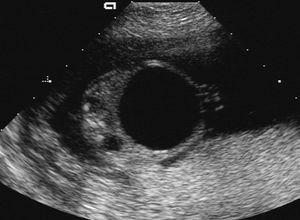

Fetal megavesica is a rare syndrome caused by morphological or functional obstruction of the fetal urethra. It is the textbook example of a single cause producing a sequence of changes in fetal development.